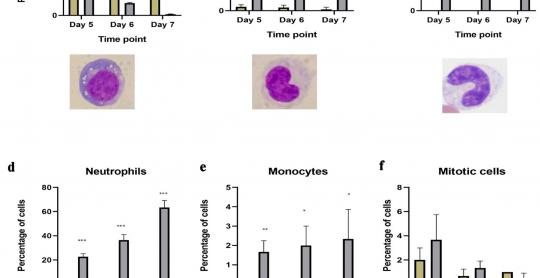

Understanding the Role of All-Trans Retinoic Acid in Acute Myeloid Leukemia Cells

World Journal of Oncology

Vol. 16, No. 6, Dec 2025, pages 574-586

By Hadeel Al Sadoun et al.

World Journal of Oncology

Vol. 16, No. 6, Dec 2025, pages 574-586

By Hadeel Al Sadoun et al.